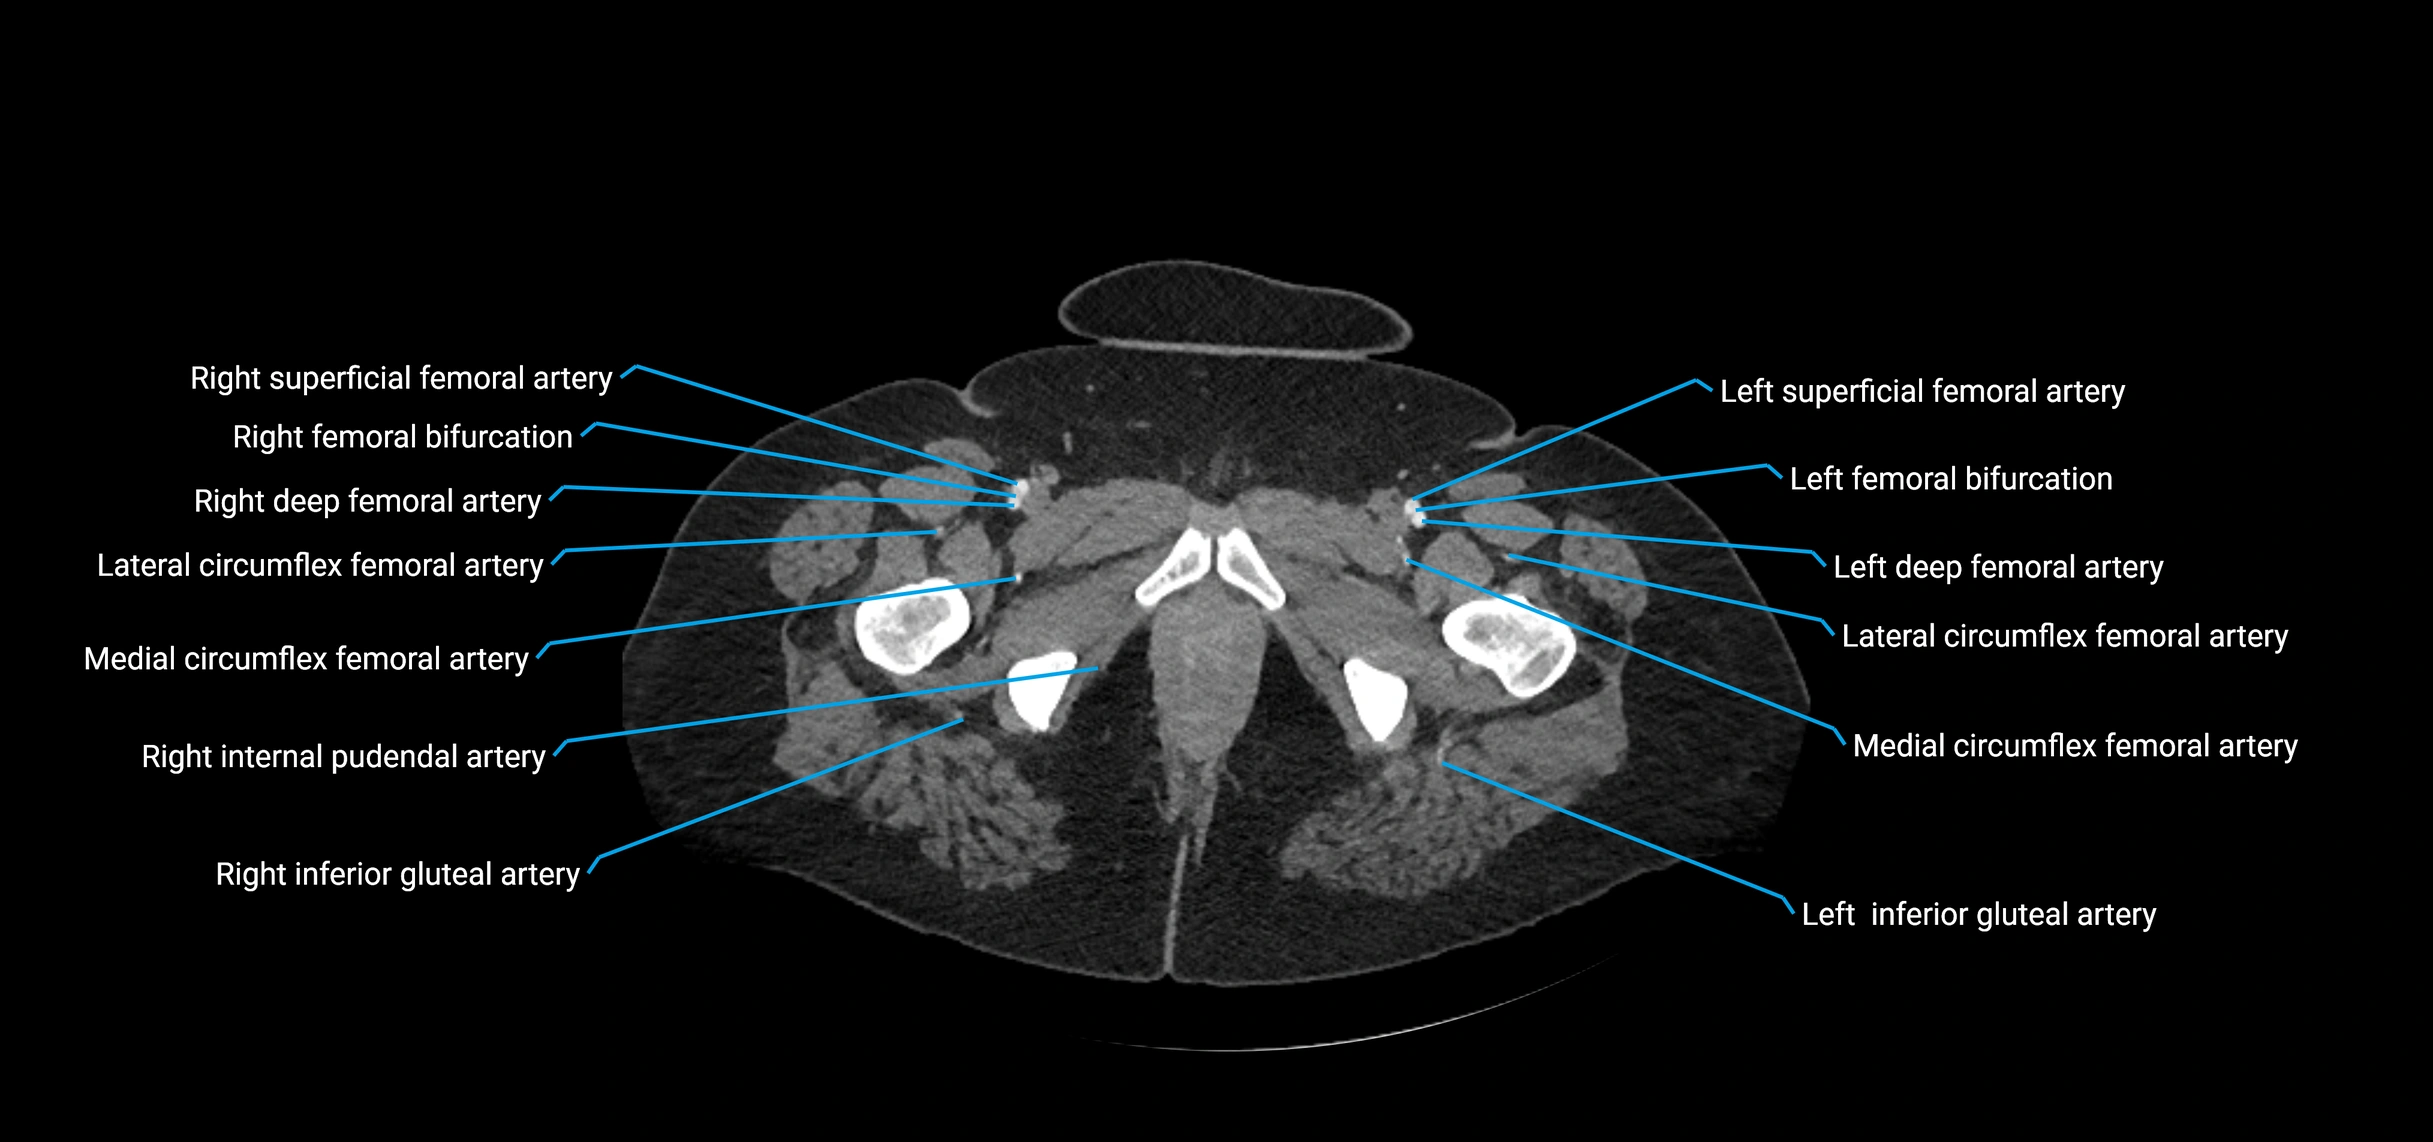

Contrast-enhanced CT (CTA):

• Gold standard for abdominal aortic imaging

• Provides excellent detail of lumen, wall, aneurysm, thrombus, and branch vessels

• Multiplanar and 3D reconstructions help in aneurysm measurement, stent graft planning, and dissection evaluation